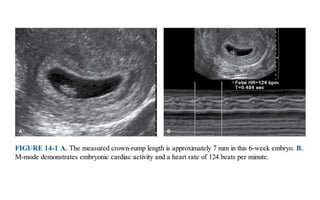

CROWN-RUMP LENGTH (CRL)

• CRL - the most accurate method to establish or confirm gestational age

(TVS - higher resolution images)

• CRL is measured in the mid-sagittal plane with the embryo or fetus in a

neutral, non-flexed position.

• Most accurate @ 7-12 weeks

• CRL EDD estimation should not be changed by subsequent scan.

CROWN-RUMP LENGTH (CRL) •CRL - the most accurate method to establish or confirm gestational age (TVS - higher resolution images) • CRL is measured in the mid-sagittal plane with the embryo or fetus in a neutral, non-flexed position. • Most accurate @ 7-12 weeks • CRL EDD estimation should not be changed by subsequent scan.